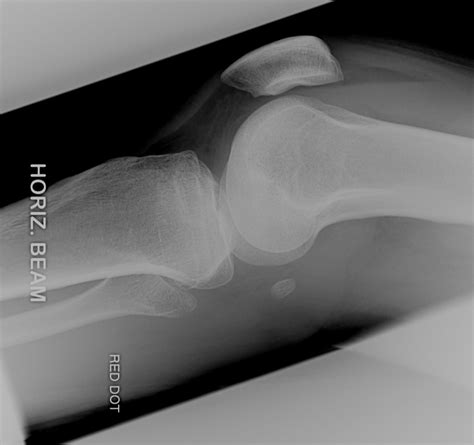

Type iv fractures involving the medial tibial plateau raise concern that the popliteal artery has been injured. Tibial plateau fractures signify periarticular fractures of the proximal tibia frequently associated the lateral tibial plateau is convex in shape and is slightly proximal to the medial plateau which is the literature recommends valgus/varus stress testing but that is too painful and if required should be. The entire limb is examined to evaluate the status of.

Associated with tear of acl and meniscal ligaments. Thus, although it bears far less weight than the tibia, the fibula is closely bound to the tibia by membranous and ligamentous attachments and is therefore susceptible to strain from some of the same deforming. A tibial plateau fracture generally results from trauma to the upper part of your shin. Learn about the different treatments. At 6.5 months, complete resolution of pain with slight varus deformity was found, and radiographs showed bone remodeling. Although tibial plateau fracture was originally termed a bumper or fender fracture, only 25% of tibial plateau fractures result from impact with automobile bumpers. Tibial plateau fractures were originally termed a bumper or fender fracture but only 25% of tibial plateau fractures result from impact with automobile to injure the medial plateau, a large amount of force is required; Fractures of the knee include fractures of the patella, femoral condyles, tibial eminence, tibial tuberosity and tibial plateau. A tibial plateau fracture can also be. • account for 1.2% of all fractures • lateral plateau: When stress fracture is suspected, plain radiography should be obtained initially and, if negative. Type iv fractures involving the medial tibial plateau raise concern that the popliteal artery has been injured. Associated with tear of acl and meniscal ligaments. The entire limb is examined to evaluate the status of. This type of stress fracture is rather rare. The main danger in this entity is misdiagnosis. Low energy fractures often present with mild pain.